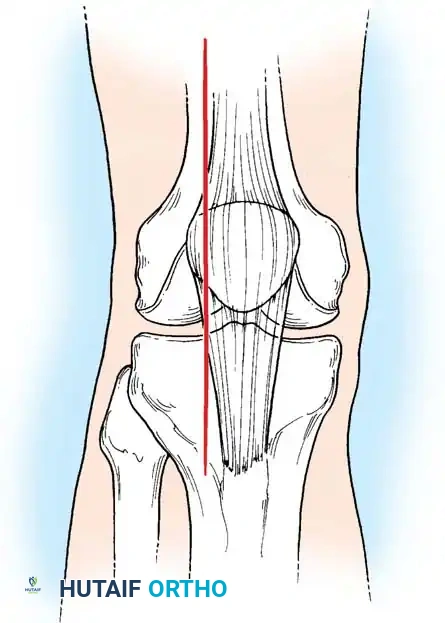

Posterolateral Femoral Condyle Fractures: The Taitsman Approach

Taitsman et al. reported successful outcomes for osteochondral fractures of the posterolateral femoral condyles treated with open reduction and internal fixation (ORIF) using countersunk screws. Preoperative Computed Tomography (CT) is mandatory to determine the exact size, location, and site of origin of the fragment.

Surgical Technique:

1. Anteromedial Incision: Utilized first to retrieve the migrated fragment from the joint space and to repair any associated medial retinacular tears resulting from patellar dislocation.

2. Posterolateral Incision: A second incision is made extending from the lateral epicondyle of the femur distally to the fibular neck.

3. Neurological Protection: The common peroneal nerve is meticulously identified and protected.

4. Deep Dissection: The deep fascia is incised between the biceps femoris tendon anteriorly and the peroneal nerve posteriorly.

5. Capsulotomy: A longitudinal capsulotomy is performed from the meniscal attachment extending to the proximal capsular reflection.

6. Fixation: The fragment is anatomically reduced and provisionally stabilized with Kirschner wires. Definitive fixation is achieved using two 2.0-mm or 2.4-mm screws.

7. Countersinking: It is critical that the screw heads are countersunk 2 to 3 mm below the articular cartilage surface to prevent iatrogenic kissing lesions on the opposing articular surface.

Image

Anatomy and surgical exposure for the posterolateral approach, highlighting the relationship between the peroneal nerve, gastrocnemius muscle, and biceps femoris tendon.

Fig. 51-76 A, Anatomy and surgical exposure. B and C, Intraoperative posteroanterior and lateral radiographs demonstrating successful screw fixation of the posterolateral condyle. (From Taitsman LA, Frank JB, Mills WJ, et al: Osteochondral fracture of the distal lateral femoral condyle: a report of two cases, J Orthop Trauma 20:358, 2006.)